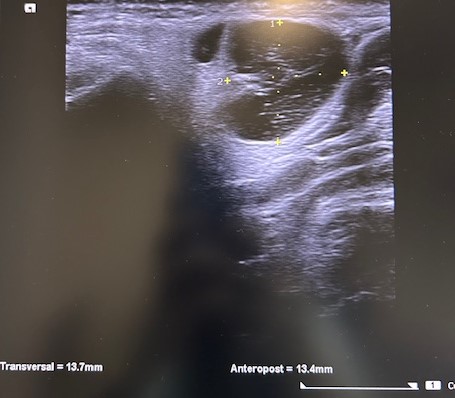

Ecografía POCUS: imagen heterogénea 1,9 x 1,7 asimétrica, con tabique en su interior, y captación de color (en modo C o con Doppler). Ante datos de mal de pronóstico solicitamos PAAF, analítica y ecografía reglada preferente.

Eco-PAAF: lesión sólida de morfología nodular posterior al ángulo mandibular derecho, con medidas aproximadas de 15 x 21 mm. Presenta ecoestructura heterogénea con áreas quísticas en su interior y con vascularización en el estudio Doppler.